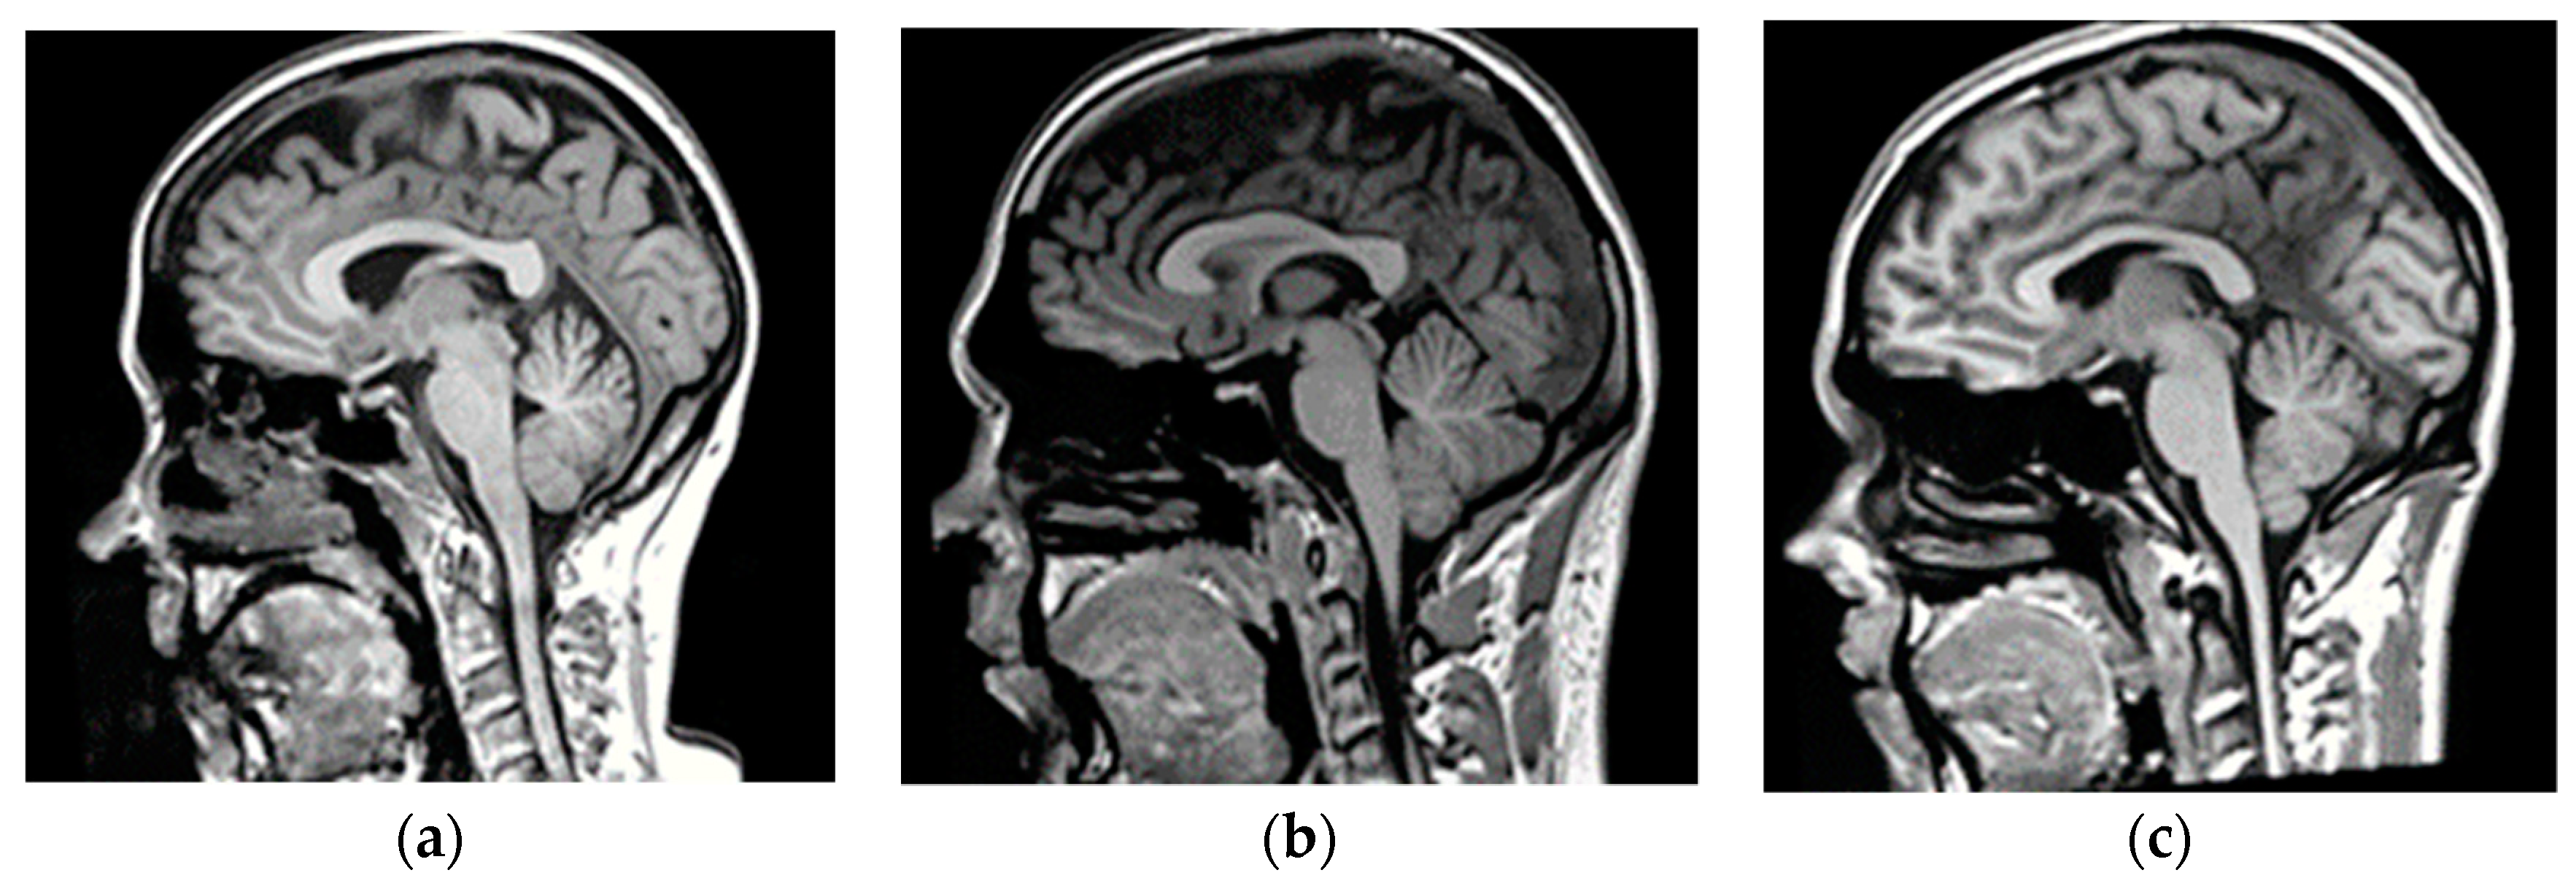

2.2. Magnetic Resonance-Computerized Tomography (MR-CT) Datasets

2.2.1. Training Dataset

2.2.2. Validation Dataset